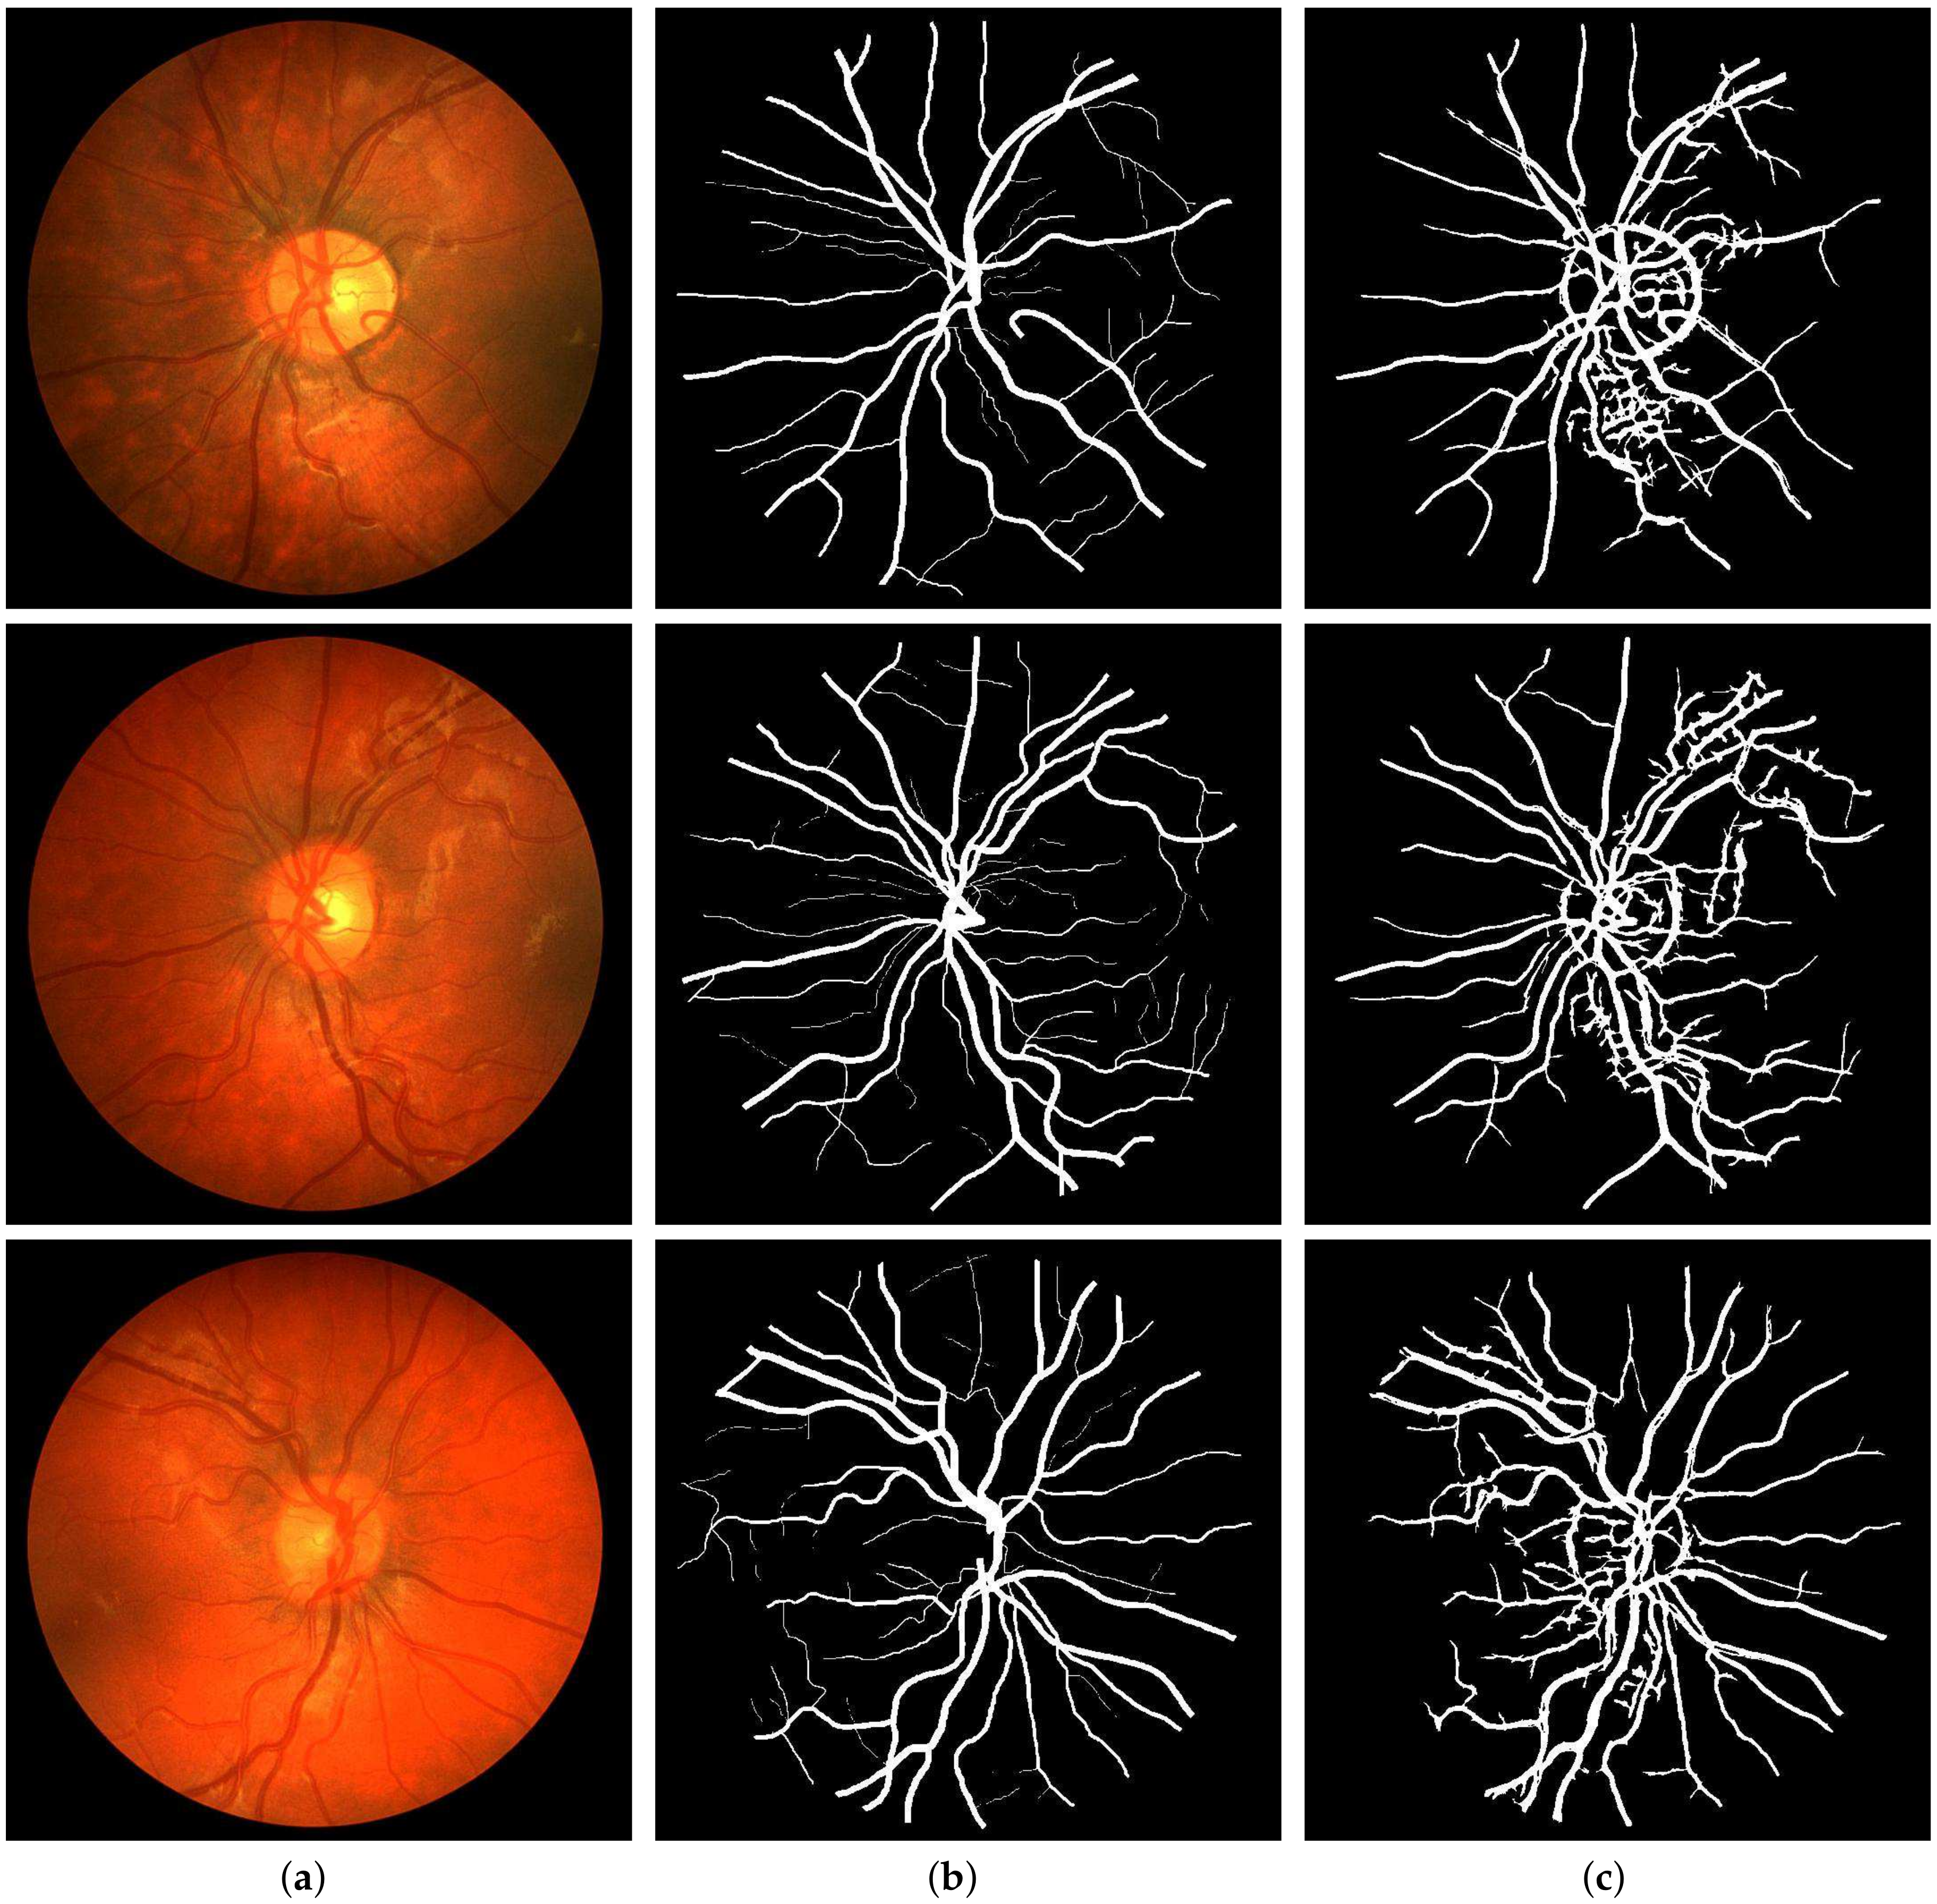

For the quantitative performance evaluation of our method, testing was carried out on the DRIVE, STARE, and CHASE_DB1 datasets with segmentation results as shown in Figure 9, Figure 10 and Figure 11, respectively. Performance measures such as Sn, Sp, and Acc for these databases are listed separately and compared with those of state-of-the-art techniques in Table 1, Table 2 and Table 3. Also, the computation time for the proposed method on MATLAB 2018b, comes out to 5 seconds per image on a Core i7 CPU (2.21 GHz, 16 GB RAM).

Figure 9. Segmentation results of DRIVE: (a) Color fundus images 3, 5 and 18; (b) Ground truths; (c) Binarization results.

Figure 10. Segmentation results of STARE: (a) Color fundus images 12, 14 and 17; (b) Ground truths; (c) Binarization results.

Figure 11. Segmentation results of CHASE_DB1: (a) Color fundus images 1, 5, and 10; (b) Ground truths; (c) Binarization results.